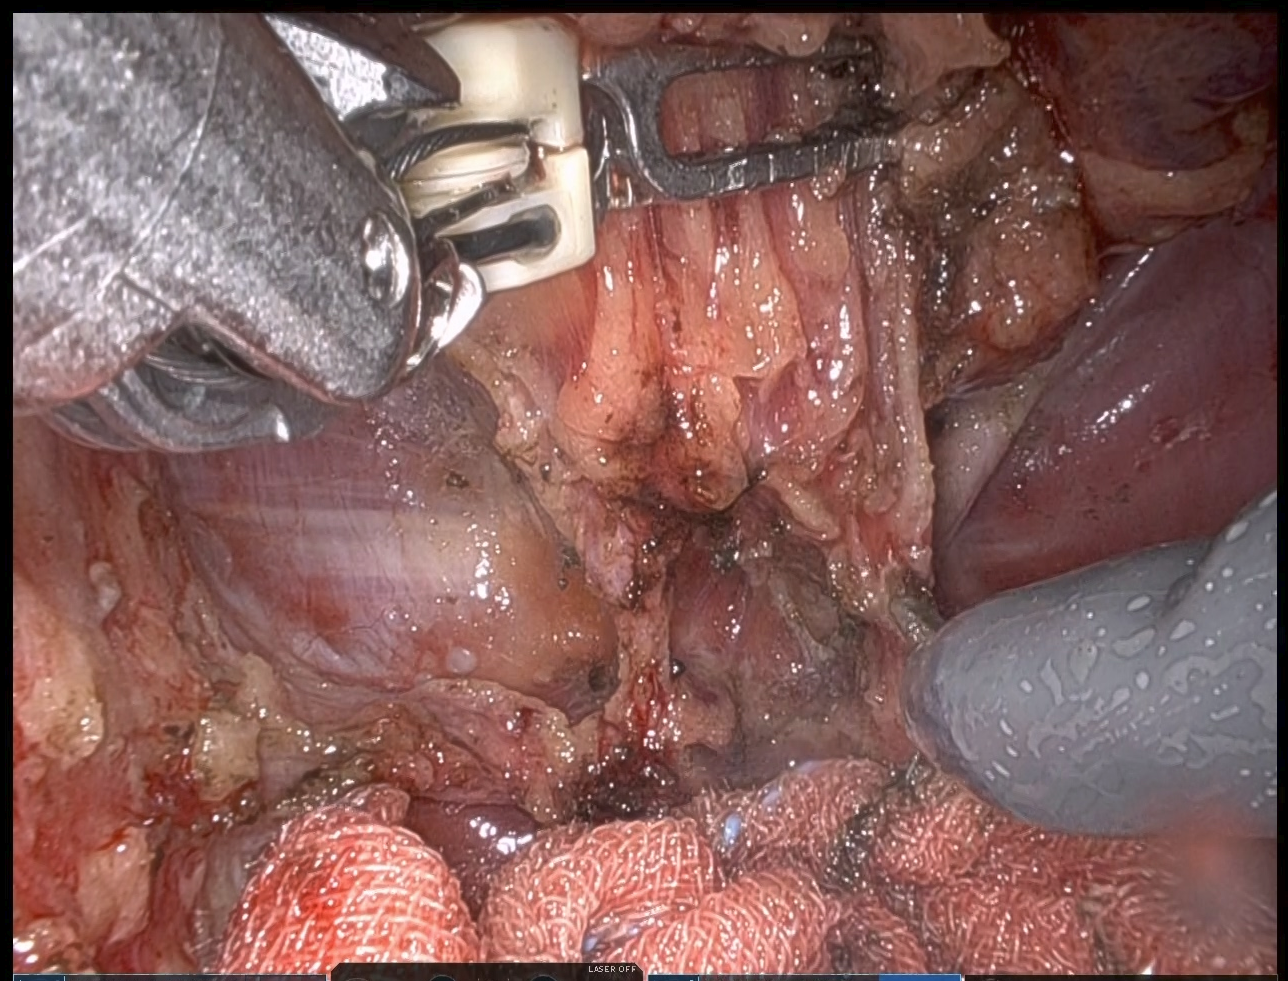

ロボット支援下手術は、腹腔鏡手術の一種として、2018年に直腸癌、2022年に結腸癌が保険収載となりました。ロボットが勝手に手術を行うわけではなく、先の腹腔鏡手術と同じように体に開けたいくつかの小さな穴から内視鏡やメス、鉗子を入れ、それらを術者が操作して手術を行います。サージョンコンソールとよばれる操縦席に術者が座り、立体画像を見ながら手元のコントローラーを操作します。

患者さんのそばにあるペイシェントカートのロボットアームにその動きが伝わり、手術を行います。鉗子を機械で制御するため、腹腔鏡手術に比べて手ぶれがほとんど無く、精緻な手術を行う事が可能です。さらに、ロボット用鉗子には関節がついており、腹腔鏡手術よりも自由度の高い手術を行うことが可能です。特に、骨盤腔のような狭い場所では効果的であり、大腸癌ガイドラインでは直腸癌に対してロボット支援下手術を行うことが強く推奨されています。

当院には2025年6月に手術支援ロボット・ダヴィンチXiが搬入され、同年8月にロボット支援下手術を開始しました。内視鏡外科技術認定取得者でかつロボット支援手術認定プロクター(消化器・一般外科)が主に執刀を行っており、順調に手術件数を伸ばしています。

手術室では液晶モニターに術者が見ている画像が映し出されます。当院では55インチの大型モニターを採用しており、助手の医師や看護師などのスタッフも同じ画像を見ながらサポートを行うため、まさにチーム一丸となって患者さんの治療を行います。